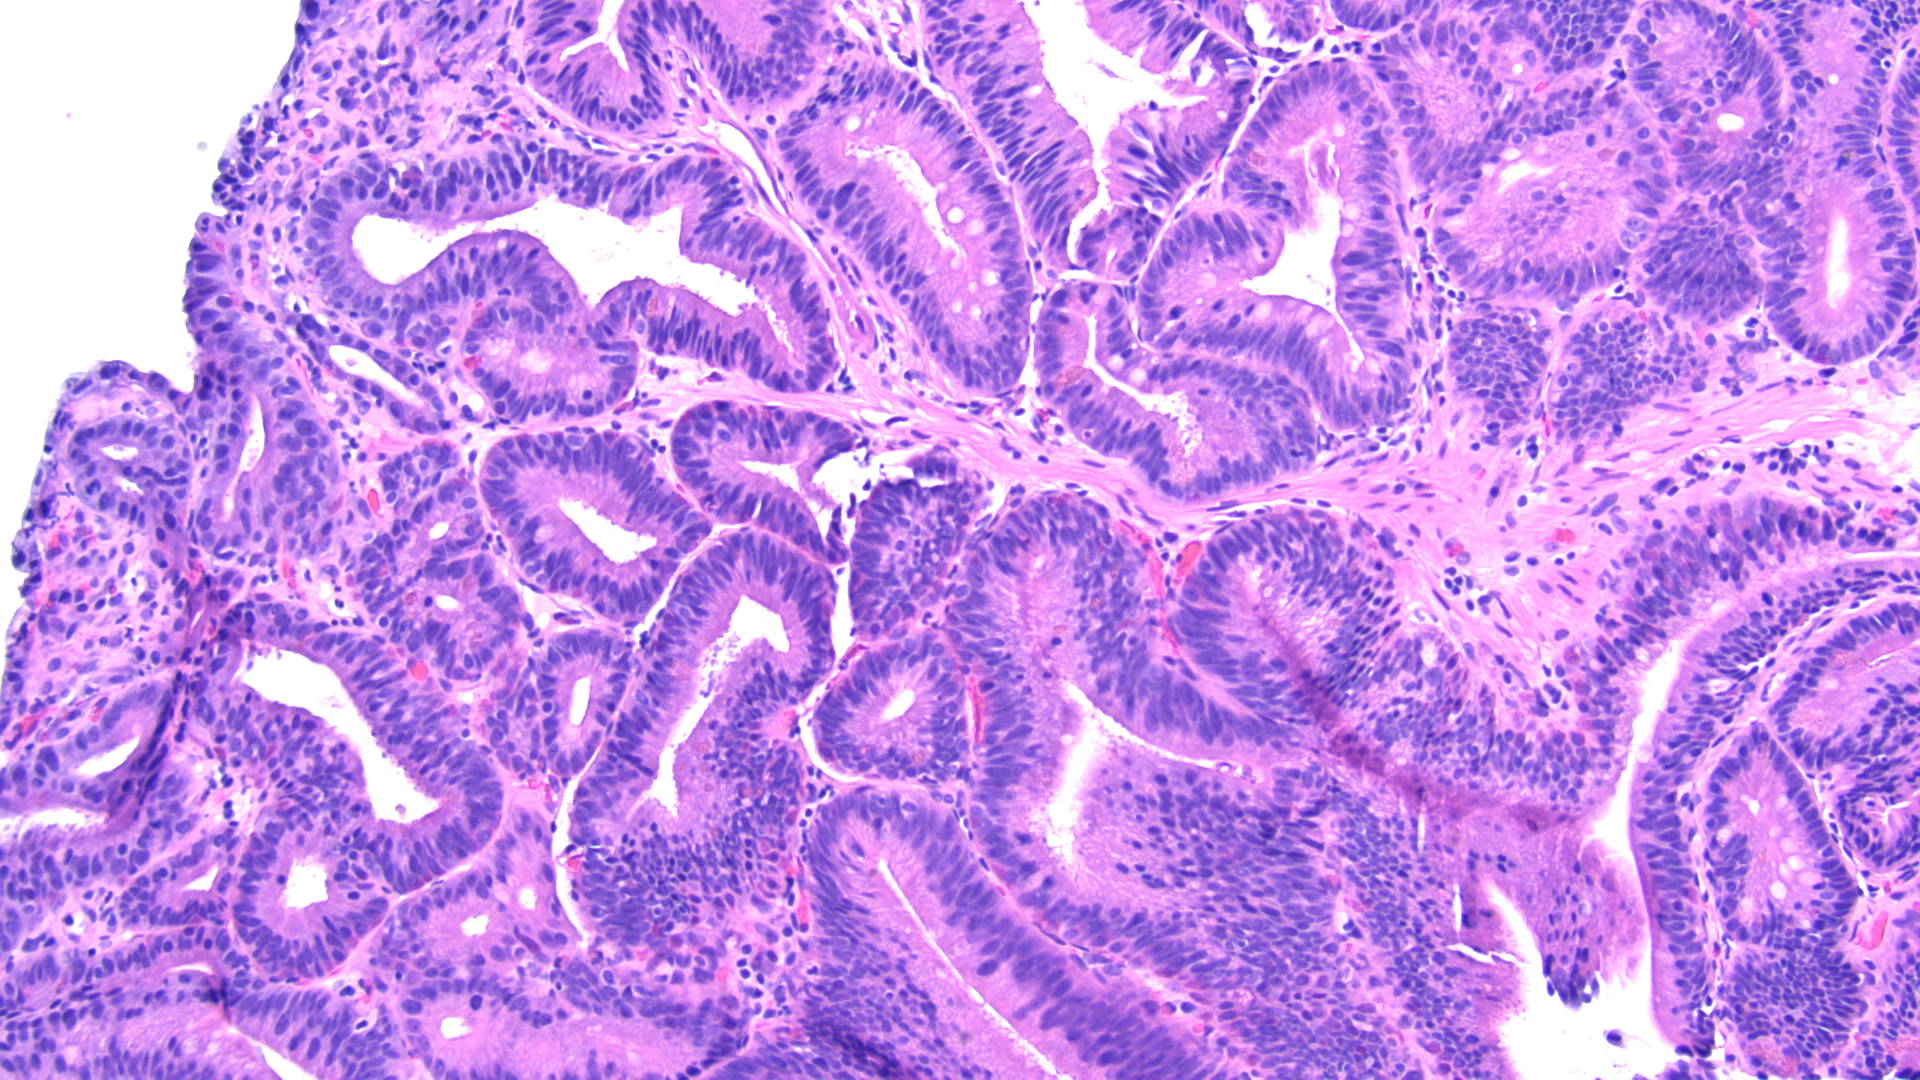

Tissue track samples resulted in the diagnosis of ampullary adenoma without evidence of high-grade dysplasia (Figures 4,5), and cytology from the brush biopsy showing atypical glandular cells. CA 19-9 levels decreased from 152 to 25 units/ml one month post-procedure. Due to a diagnosis of ampullary adenoma, the patient and her family were counseled on ampullectomy to prevent ampullary cancer versus watchful waiting. They elected to pursue ampullectomy. The procedure was performed under general anesthesia. A side viewing duodenoscope was advanced to the second part of the duodenum. The previously placed biliary stent was retrieved using a snare.  The scope was then repositioned to visualize a large 3.5 cm ampullary adenoma (Fig 1). Cholangioscopy (spyglass Boston Scientific) also revealed possible skip lesions versus changes from the prior stent in the bile duct.  Submucosal injection was then performed and the lesion lifted from the wall showing that it was not fixed to the side of the duodenum.  A 27 mm Captivator snare was used to perform ampullectomy which was retrieved using a Roth net.  A residual lesion on the margin was removed using a 15 Captivator, also retrieved using a Roth net.  After ampullectomy, cannulation of the pancreatic duct was achieved using Jagwire Revolution (Boston Scientific), after which a 5 cm French single pigtail pancreatic stent was placed.  The bile duct was also cannulated, after which double-pigtail 7 cm 10 French plastic biliary stent was placed with good biliary drainage (Figures 2,3).  Margins were ablated using Argon plasma coagulation to prevent adenoma recurrence. Histopathology showed intestinal type ampullary adenoma with low grade dysplasia and no invasive adenocarcinoma (Figures 6,7). One month later, ERCP was conducted during which both the double and single pigtail stents were removed, and further interrogation of the bile duct with cholangioscopy revealed no skip lesions suggesting that the observed small changes were due to the previous metal stenting. A 60mm x 10mm self-expanding metal biliary wall stent (Boston Scientific) was placed with good biliary drainage. The patient tolerated both procedures well without any adverse event.

Figure 6 – Ampullary adenoma tissue analysis, 40x magnification

Figure 7 – Ampullary adenoma tissue analysis, 100x magnification